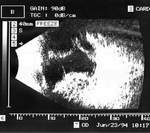

Rycina 9. Stan po opasaniu gałki ocznej wykonanym jako leczenie pourazowego odwarstwienia siatkówki. Widoczny wał opasania oraz liczne hiperechogeniczne zagęszczenia ciała szklistego, siatkówka jest przyłożona